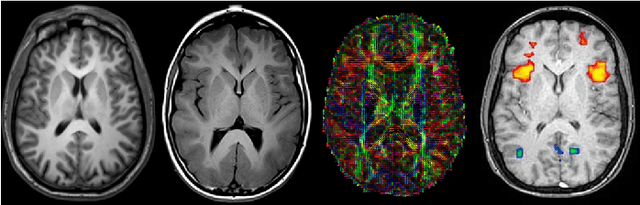

Abstract:Identifying and characterizing brain fiber bundles can help to understand many diseases and conditions. An important step in this process is the estimation of fiber orientations using Diffusion-Weighted Magnetic Resonance Imaging (DW-MRI). However, obtaining robust orientation estimates demands high-resolution data, leading to lengthy acquisitions that are not always clinically available. In this work, we explore the use of automated angular super resolution from faster acquisitions to overcome this challenge. Using the publicly available Human Connectome Project (HCP) DW-MRI data, we trained a transformer-based deep learning architecture to achieve angular super resolution in fiber orientation distribution (FOD). Our patch-based methodology, FOD-Swin-Net, is able to bring a single-shell reconstruction driven from 32 directions to be comparable to a multi-shell 288 direction FOD reconstruction, greatly reducing the number of required directions on initial acquisition. Evaluations of the reconstructed FOD with Angular Correlation Coefficient and qualitative visualizations reveal superior performance than the state-of-the-art in HCP testing data. Open source code for reproducibility is available at https://github.com/MICLab-Unicamp/FOD-Swin-Net.

Abstract:Medical image segmentation is an increasingly popular area of research in medical imaging processing and analysis. However, many researchers who are new to the field struggle with basic concepts. This tutorial paper aims to provide an overview of the fundamental concepts of medical imaging, with a focus on Magnetic Resonance and Computerized Tomography. We will also discuss deep learning algorithms, tools, and frameworks used for segmentation tasks, and suggest best practices for method development and image analysis. Our tutorial includes sample tasks using public data, and accompanying code is available on GitHub (https://github.com/MICLab-Unicamp/Medical-ImagingTutorial). By sharing our insights gained from years of experience in the field and learning from relevant literature, we hope to assist researchers in overcoming the initial challenges they may encounter in this exciting and important area of research.